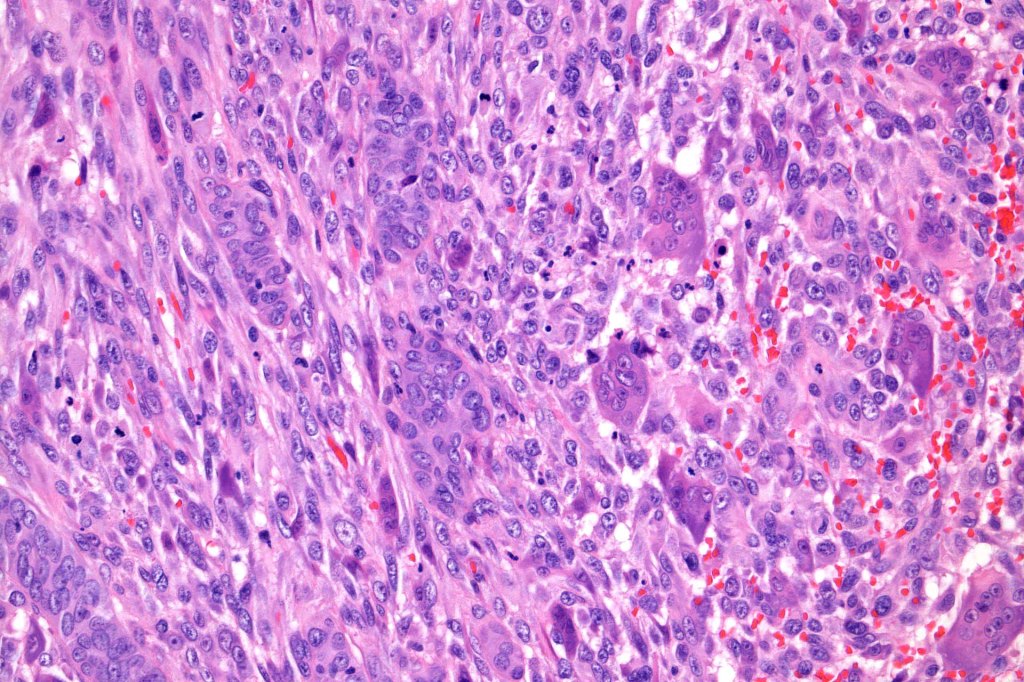

Carcinosarcoma

Cutaneous carcinosarcoma (metaplastic carcinoma, carcinoma with heterologous differentiation)

Histological features

•Osteoid

•Chondroid

•Smooth muscle

•MFH-like features with osteoclasts

•Neural differentiation